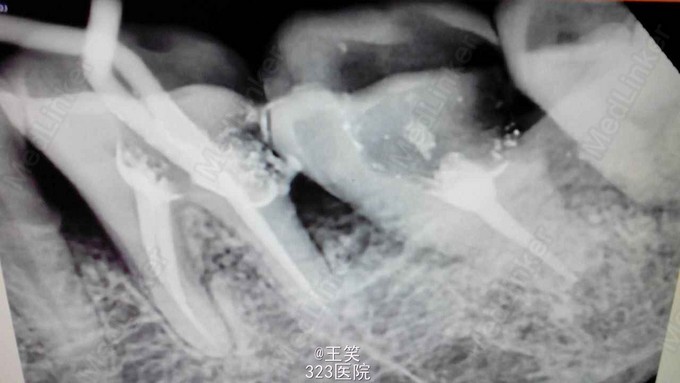

36.37远中邻面牙颈部龋坏,36探(++),叩(+—),冷热诊激发痛,37探(+),叩(-),冷热诊敏感。 X线示:36龋坏至髓腔,牙周膜少于增宽,37龋坏近髓腔。

诊断:36牙髓炎 37深龋? 建议:36.37行RCT+桩+冠修复 处理:‘局’麻下,36去腐,开髓,揭全髓顶,根管预备,常规充填。37腐未去净露髓,去净腐质,开髓,揭全髓顶,根管预备'常规充填。 医嘱:勿食硬粘物,一周复诊。